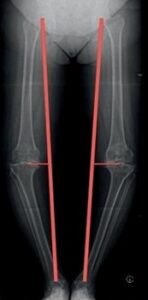

Unfallbedingte Verletzungen des Gelenkes sowie längerfristige Über- und Fehlbelastung können zu einer Schädigung der Knorpeloberfläche mit fortschreitendem Gelenkverschleiß (Arthrose) führen. Die Kniegelenksarthrose bezeichnet der Arzt als „Gonarthrose“. Der menschliche Körper kann den Verlust des Knorpels nicht ersetzen. Achsfehlstellungen (Abb. 2) führen zu einem schnellen Fortgang des Erkrankungsbildes.